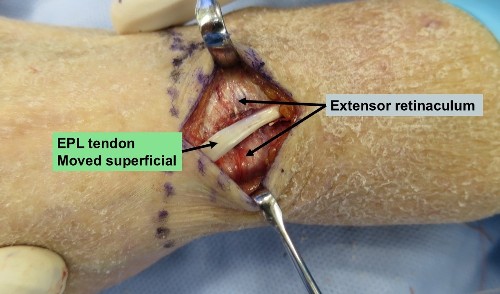

- EPL Decompression - Removing the EPL from the groove adjacent to Lister’s tubercle & placing it superficial to the retinaculum